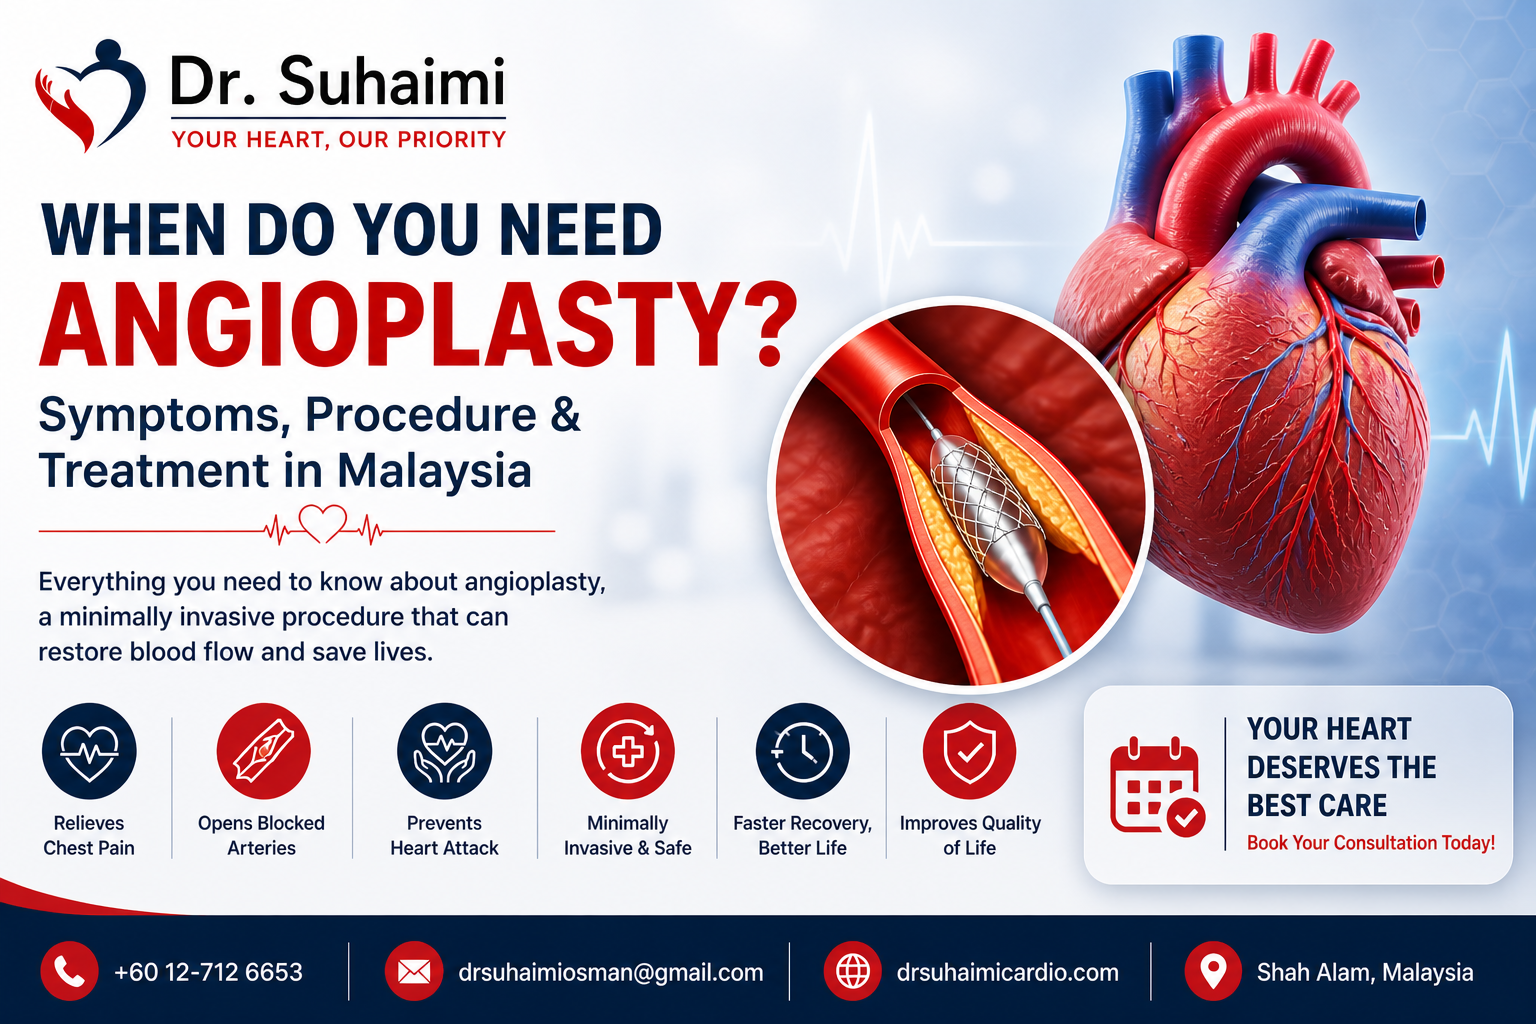

Interventional Procedures

Expert in angioplasty, stenting, and minimally invasive procedures to restore heart function effectively and improve patient recovery outcomes.

Coronary Artery Disease

Managing blocked arteries with interventions to restore blood flow and reduce heart attack risk.

Chest Pain & Angina

Accurate diagnosis and treatment to relieve chest discomfort and prevent serious heart conditions.

Ongoing monitoring and recovery plans after angioplasty, stenting, or other cardiac interventions.

Interventional cardiology uses minimally invasive procedures like angioplasty and stenting to treat blocked arteries, restore blood flow, and prevent heart attacks. It offers faster recovery, less pain, and avoids the risks of open-heart surgery.